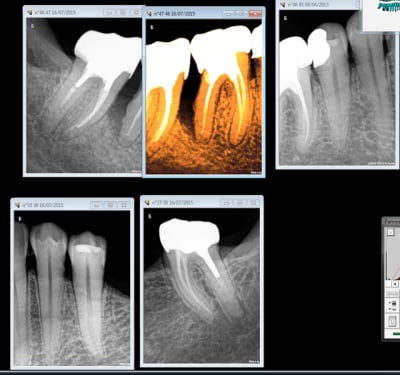

Je comprends pas ce que ça veut dire "ceux qui sont passé au NPNC". Ils font quoi là par exemple? (désolé j'arrive par à l'exporter avec traitement et rotation)

Là sans doute un implant.

Et là tu fais quoi sur la 25 qui est symptomatique et qui présente un magnifique pan d'émail en vestibulaire ?

Pas meme de réponse au froid ? Ben un onlay vas y fonces ! -)))))